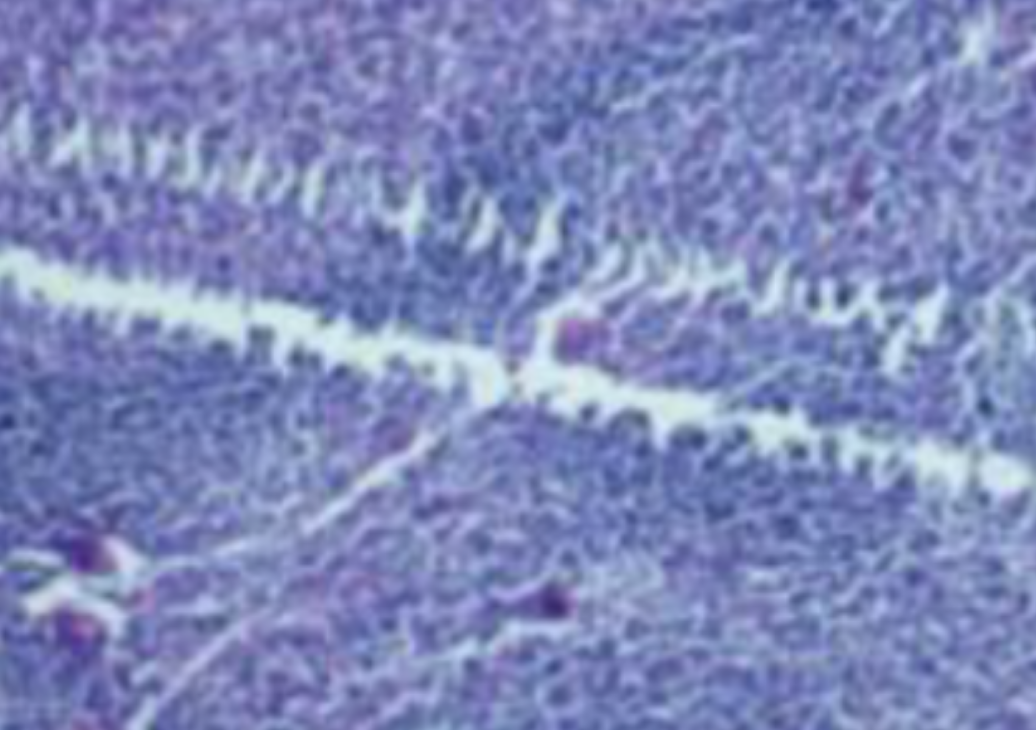

HE染色,全称苏木精-伊红染色法(Hematoxylin and Eosin staining),是最常见的组织切片染色技术之一,用于在显微镜下观察和分析组织或细胞的结构和形态。虽然HE染色是最常见且最基础的染色技术之一,😭但在实验过···

HE染色,全称苏木精-伊红染色法(Hematoxylin and Eosin staining),是最常见的组织切片染色技术之一,用于在显微镜下观察和分析组织或细胞的结构和形态。

虽然HE染色是最常见且最基础的染色技术之一,😭但在实验过程中,很容易出现各种情况导致染色切片质量参差不齐。所以,小编根据以往实验经验,给大家整理归纳出了15个HE染色中的常见问题,还包含问题原因分析以及解决方法哦~

形成原因:切片经梯度乙醇处理后没有完全脱水,导致二甲苯透明、中性树胶封固后残留大量水分。 解决方法:首先移去盖玻片,用二甲苯溶解封固剂如中性树胶,再将切片置入无水乙醇内,待切片重新脱水完全后,用二甲苯透明处理,中性树胶封固。要注意所有用于脱水和透明的液体,在使用一定时间后,应及时更换。 二、细胞核呈红、棕色 形成原因:苏木精染色液过度氧化,切片在苏木精染液染色后返蓝不足。 解决方法:每次染色之前检查苏木精染色液的染色能力,发现苏木精染色液氧化过度应及时更换。此外,切片经苏木精染色后,要给切片以足够的蓝化时间,蓝化过程可用流水、温水、弱碱性溶液(如稀氨水或0.2%碳酸氢钠)等处理。 三、切片在脱蜡后出现大片白色斑点 形成原因:由于烤(烘)片温度太低,切片上的组织蜡膜在脱蜡前没有充分烤(烘)融化。或是因为切片在二甲苯液中停留时间不足,或二甲苯使用过久,造成的脱蜡不彻底。 解决方法:若是由于切片烤(烘)温度低所致,可以先用二甲苯去除切片上的封固胶,然后重新用二甲苯脱去切片上的石蜡,再进行后续染色。若是由于切片在脱蜡的二甲苯中停留时间不足或脱蜡二甲苯使用过久浓度不足所致,则需将切片退回到二甲苯中,停留较长时间,或更换二甲苯液体重新脱蜡,再入乙醇重新脱二甲苯,入0.5%盐酸水溶液褪色后,重新HE染色。 四、细胞核苍白暗淡,即苏木精染色太淡 形成原因:切片在苏木精染色液停留时间太短;苏木精染色液过度氧化,失去染色能力,不能再继续使用;分化步骤处理时间过长;固定不及时。此外值得注意的是,若骨组织细胞核暗淡,大多是脱钙过度造成的。 解决方法:切片重新染色。如果组织在酸性固定液(如Zenker、Bouin)或非中性缓冲甲醛液固定时间过长,细胞核染色能力将减弱,需增加其在苏木精染色液的时间,或用一些方法增加组织的嗜碱性,以改善细胞核的着色。例如,上述组织玻片可以使用Weigert铁苏木精染色液。如果组织是用Zenker液固定的,可将切片脱蜡后放在5%碳酸氢钠溶液3~4h,流水冲洗5min后染色。如果组织是用Bouin液固定的,可将切片脱蜡后放在5%碳酸锂1h,流水冲洗10min后染色。 五、细胞核过染,苏木精染液占据了细胞质 形成原因:玻片在苏木精染色液停留时间过长,或是切片太厚、分化步骤时间太短。 解决方法:如果不是因为切片太厚(用显微镜仔细上下微调,只有一二层细胞核层次),就需将切片进行脱色、漂白、重新染色,适当调整染色和分化时间。但如果确定是由于切片太厚导致的细胞核过染,则需要重新切片。 六、伊红着色淡 形成原因:可能是伊红染液pH值大于5,也可能是蓝化液残留过多,切片太薄,或是切片经伊红染色后在乙醇脱水时间过长。 解决方法:检查伊红染液pH值,必要的话,用乙酸将其调节在4.6~5.0之间,从而使伊红染色色彩艳丽。此外,确保每次蓝化步骤完成后,使用的弱碱性溶液被充分洗去,玻片上没有残留的弱碱性溶液。最后,检查切片的厚度,且脱水时不要让切片在低浓度乙醇中停留时间过长,因为含水多的低浓度乙醇会将切片伊红的颜色分化掉。 七、细胞质过染、分色不足 形成原因:伊红染色液浓度太高,特别是存在焰红燃料、四溴四氯荧光素钠。切片在伊红染色时间过长,或是切片在伊红染色后经乙醇脱水步骤时时间太短,而使乙醇分化伊红的作用不能产生,都能够使细胞质过染。 解决方法:适当稀释伊红染色液,减少伊红染色时间,或使切片在乙醇脱水等步骤时,停留时间相对均匀。同样,也要检查切片的厚度是否合适。 八、切片中出现蓝黑色沉淀物 形成原因:苏木精染色液中的金属膜黏附在玻片上。 解决方法:染色前仔细过滤苏木精染色液,建议使用半氧化苏木精染色液,如Gill苏木精染色液,可以避免过多的金属膜产生。 九、光镜下切片某些区域难以聚焦 形成原因:盖玻片上可能有封固切片的封固剂。 解决方法:移去盖玻片,重新用干净的盖玻片封片。检查切片封片方法,是人工手工封法,还是机器自动封法,如有问题及时调整。 十、封固剂从盖玻片与载玻片之间的缝隙回缩 形成原因:盖玻片弯曲或不平整,或是封固剂含二甲苯过多,稀释过度。 解决方法:移去盖玻片,重新找一张盖玻片,用干净的封固剂封片。如用手工封片法,保证在封固结束时,封固剂容器盖子为紧闭状态。且尽量使用小的容器盛装封固剂,一旦封固剂太黏稠,就可以选择废弃。 十一、细胞核呈灰蓝状态 形成原因:可能由于组织处理温度过高、过热,在液体石蜡中停留的时间过长。或是固定时间太短后,直接在高浓度的乙醇中进行了脱水处理。 解决方法:理论上来说,仅在组织浸蜡步骤才进行加热,组织不能在热蜡液中停留太久。如果由于某些原因不能进行下一步包埋处理,可将组织连同塑料包埋盒一并放置在室温空气中,冷却凝固,以备包埋。待需要包埋时再重新加温直至石蜡融化即可。组织在处理前必须确保固定良好,脱水最好能从低浓度的乙醇开始。 十二、类色素的点状结晶和黑色光滑细胞核 形成原因:这种裸核改变是因为切片封片前放置在空气中的时间太长,以至于二甲苯挥发,切片干燥。 解决方法:移去组织切片上的盖玻片和封固剂,重新处理。将切片水洗数分钟,然后重新脱水、透明、封固。封片过程中要保持组织切片的轻度湿润,尽量不要让其干燥。 十三、染色过淡或过浓 解决方法:如果染色过淡,可以增加染色剂的浓度、延长染色时间或更换新鲜的染色剂;如果染色过浓,则应减少染色剂的浓度或缩短染色时间。 十四、切片出现叠加褶皱 形成原因:新购买的玻片洁净度不够、用镊子撑开切片时操作不够熟练未能平整伸展,或玻片表面有油脂,切片粘贴不牢。另外,烤片时间不足、烤片温度过低或切片过厚造成切片脱落,都会造成重叠或有皱褶的情况。 解决方法:新购买的玻片最好能用硫酸清洁液浸泡一晚,然后流水冲洗干净。在适宜的温度下烤片时间宁长勿短,保证有充足的烤片时间和温度。另外,切片刀要锋利,才能切出厚薄适宜的切片,保证切片不会因为过厚而脱落。 十五、组织残缺不全或有刮划痕迹 形成原因:组织残缺不全是由于切片时修整蜡块时深度不够、组织没有全部暴露于切面。切片的刮划痕迹是由于切片刀的刀锋有缺口、包埋的组织有异物,或是钙化组织、骨组织及包埋石蜡有沙粒造成的。 解决方法:修整蜡块时保证组织块全部暴露于切面,切片时保证切片刀的锋利没刀口。同时在组织取材时去除手术异物和钙化组织。最后,骨组织要完全脱钙,这样可以保证切片的完整和平整美观。 *注:由于实验中导致结果出现误差的原因多种多样,以上内容仅供参考,具体根据实际情况进行判断。